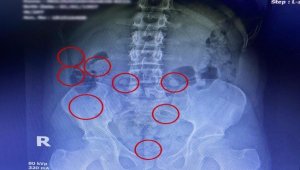

Uyuşturucular röntgenle çıktı